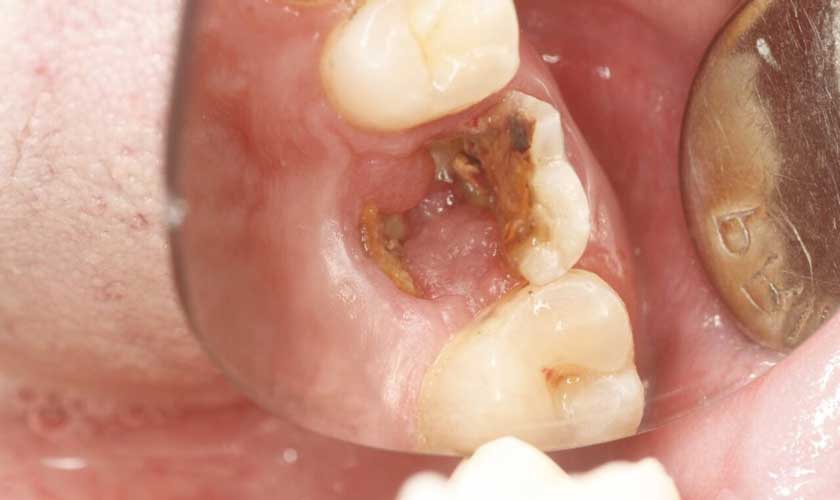

Trường hợp sâu chân răng ở giai đoạn nghiêm trọng, tủy răng bị phá hủy thì cần tiến hành chữa tủy và loại bỏ mô răng bị sâu rồi bọc răng sứ để phục hồi ăn nhai, thẩm mỹ cho răng.

Trường hợp sâu chân răng không thể phục hồi thì cần tiến hành nhổ răng để tránh vi khuẩn tấn công vào xương hàm và các răng khác, phá hủy cấu trúc xương hàm và gây sâu răng diện rộng.